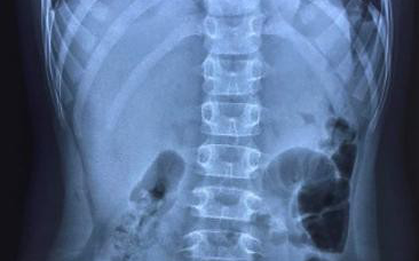

Nuốt hơn 30 viên nam châm, bé trai thủng 8 lỗ ở ruột

Ngày 19/9, BS Nguyễn Hiền, khoa Ngoại Tổng hợp, Bệnh viện Nhi Đồng 2 TPHCM cho biết, tại đây vừa tiếp nhận và can thiệp cho trường hợp trẻ bị thủng ruột, nguy hiểm tính mạng vì nuốt nam châm đồ chơi. -